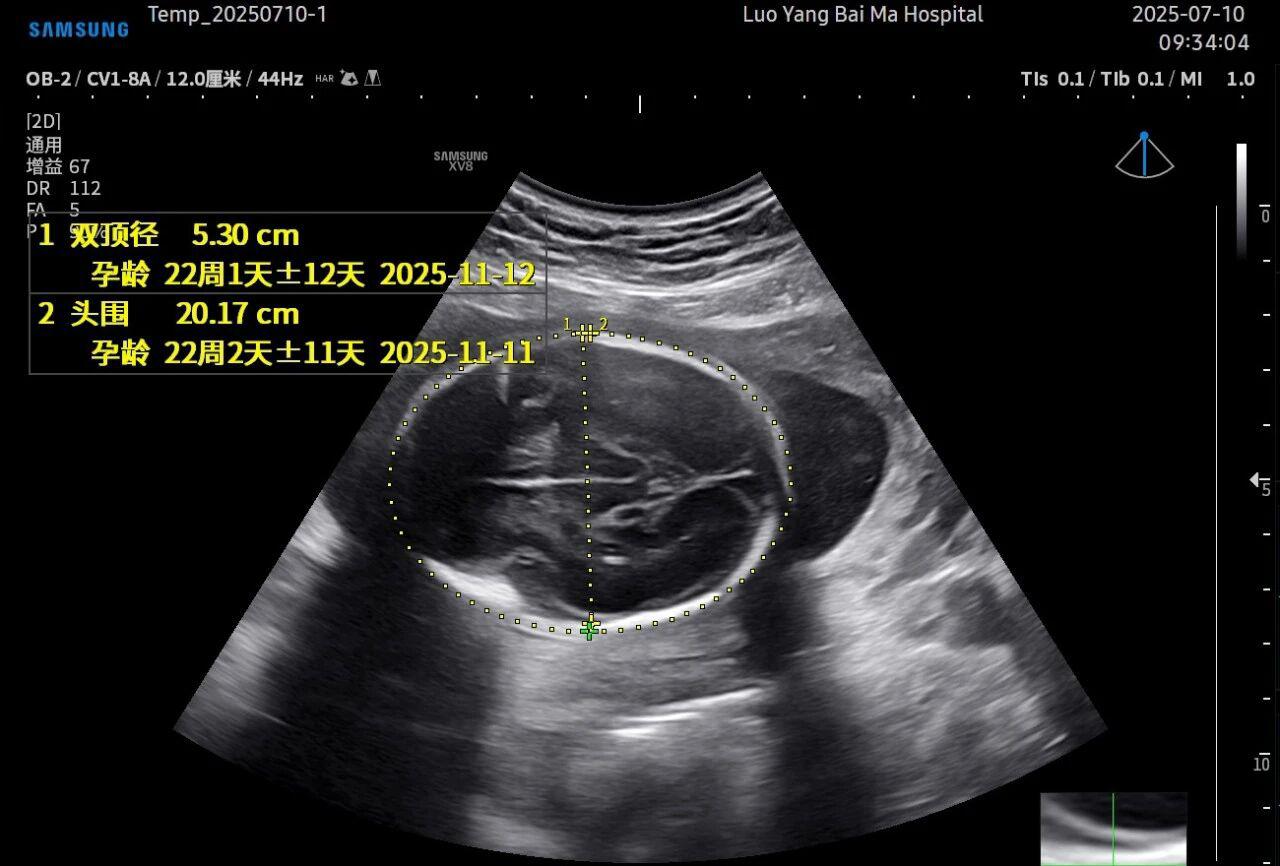

孕中期(通常在22-28周)的大排畸检查是整个孕期至关重要的环节之一。其目的在于系统地筛查胎儿是否存在结构性异常,如唇裂、脊柱裂、大脑、心脏、骨骼发育不良等问题。在这一关键检查中,5D智能彩超凭借其技术特性,展现出了显著的优势。

5D智能彩超拥有更高的分辨率和更强的图像处理能力,能够呈现出接近“IMAX电影画质”的细腻影像 。它采用一种被称为“水晶成像”的技术,能够穿透组织,将胎儿的骨骼、器官和组织结构以极其清晰、立体的形态展示出来。这种高清晰度对于观察胎儿微小的解剖结构细节至关重要,例如手指、脚趾、耳廓形态等,有助于医生发现一些在传统超声下不易察觉的细微异常,为排畸诊断提供了更丰富的视觉信息。

这是5D技术的核心优势之一。系统内置了强大的智能化大数据分析功能和AI辅助诊断工具。例如,在进行胎儿颈项透明层(NT)测量、胎儿长骨(LB)测量等关键生物学指标评估时,5D智能系统可以自动识别解剖层面、智能勾勒测量范围并进行计算。这不仅大大缩短了检查时间,更重要的是,它通过标准化的智能算法减少了因人为操作可能产生的误差,使诊断结果更加客观、可靠。